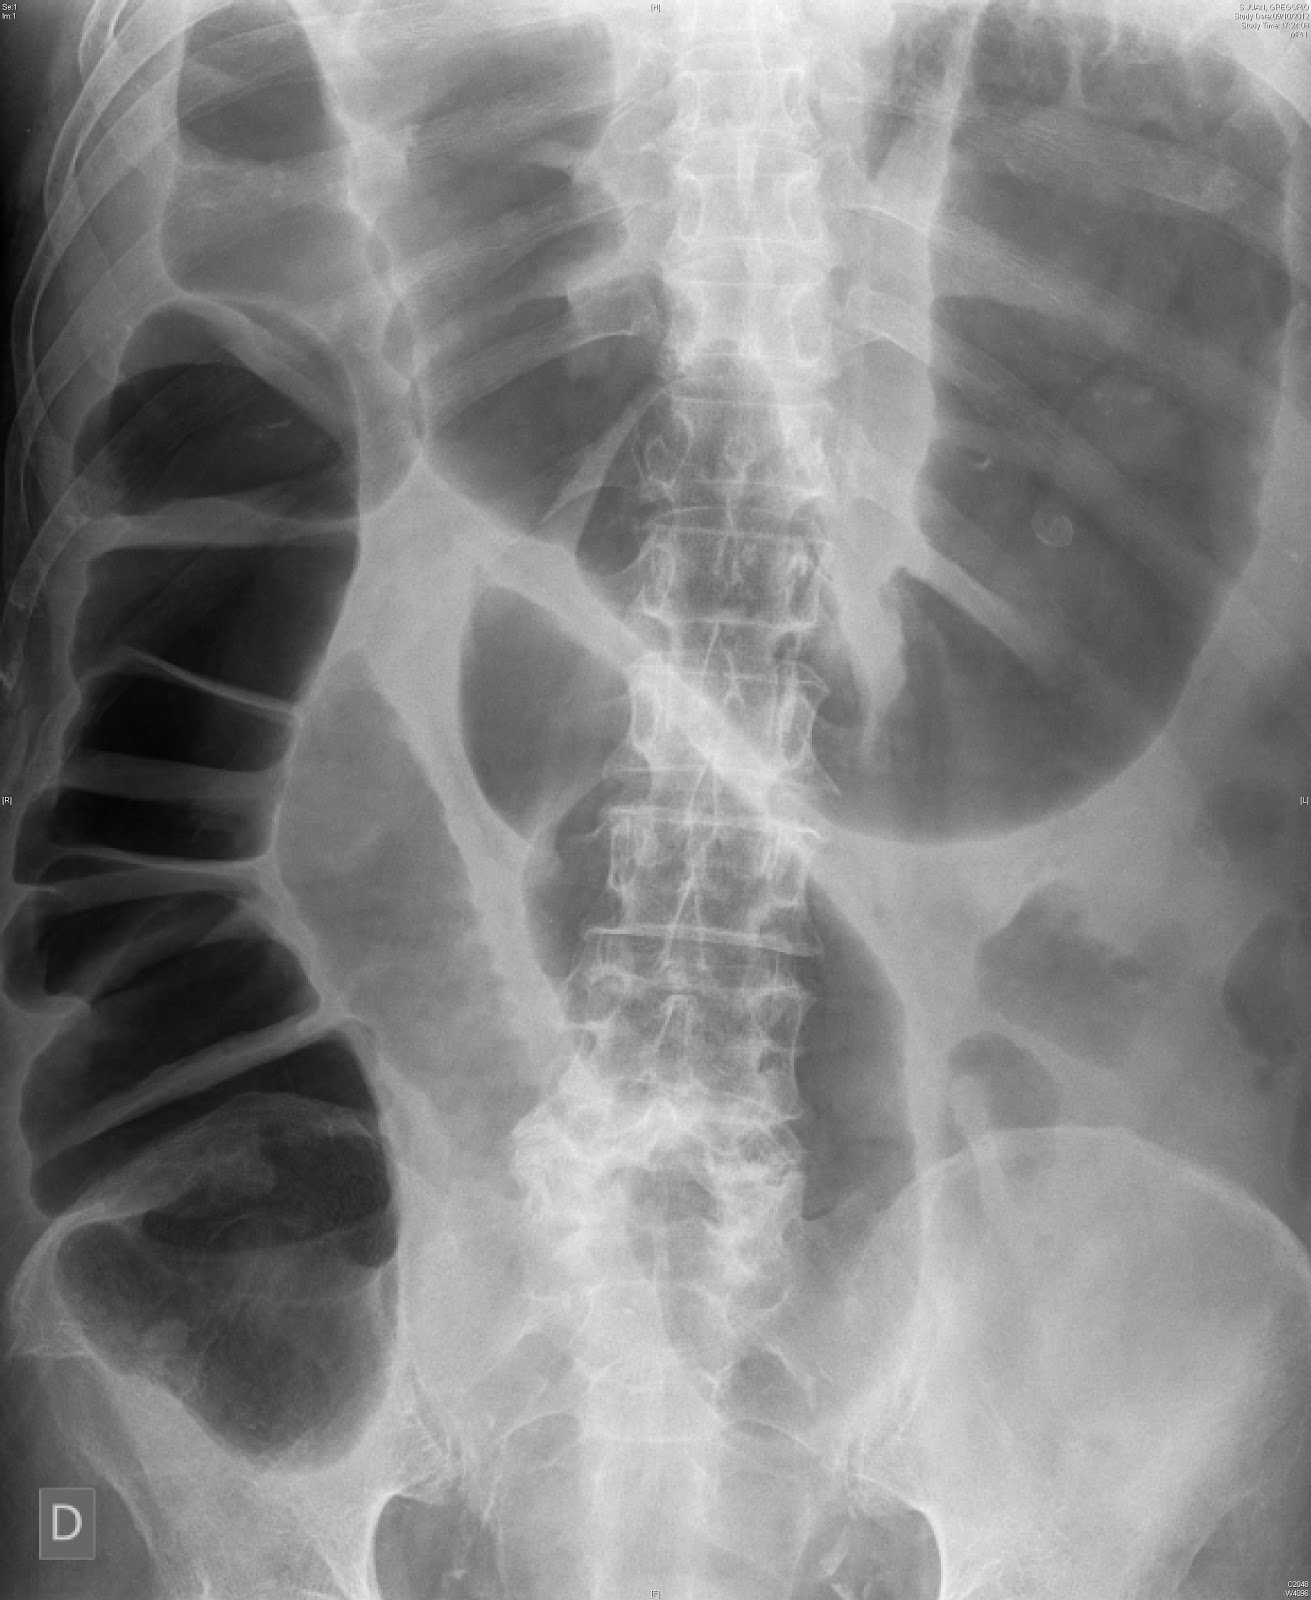

From www.wikidoc.org

Ogilvie syndrome x ray wikidoc Ogilvie Collision oglivie collision auto body & restoration is open mon, tue, wed, thu, fri. we're fully equipped with all the automotive body repair tools, equipment, and skilled labor to deliver the best service to you. ogilvie collision is a reputable auto body repair shop in ogilvie, mn, specializing in collision repair services. Body shops, auto glass services. Ogilvie Collision.